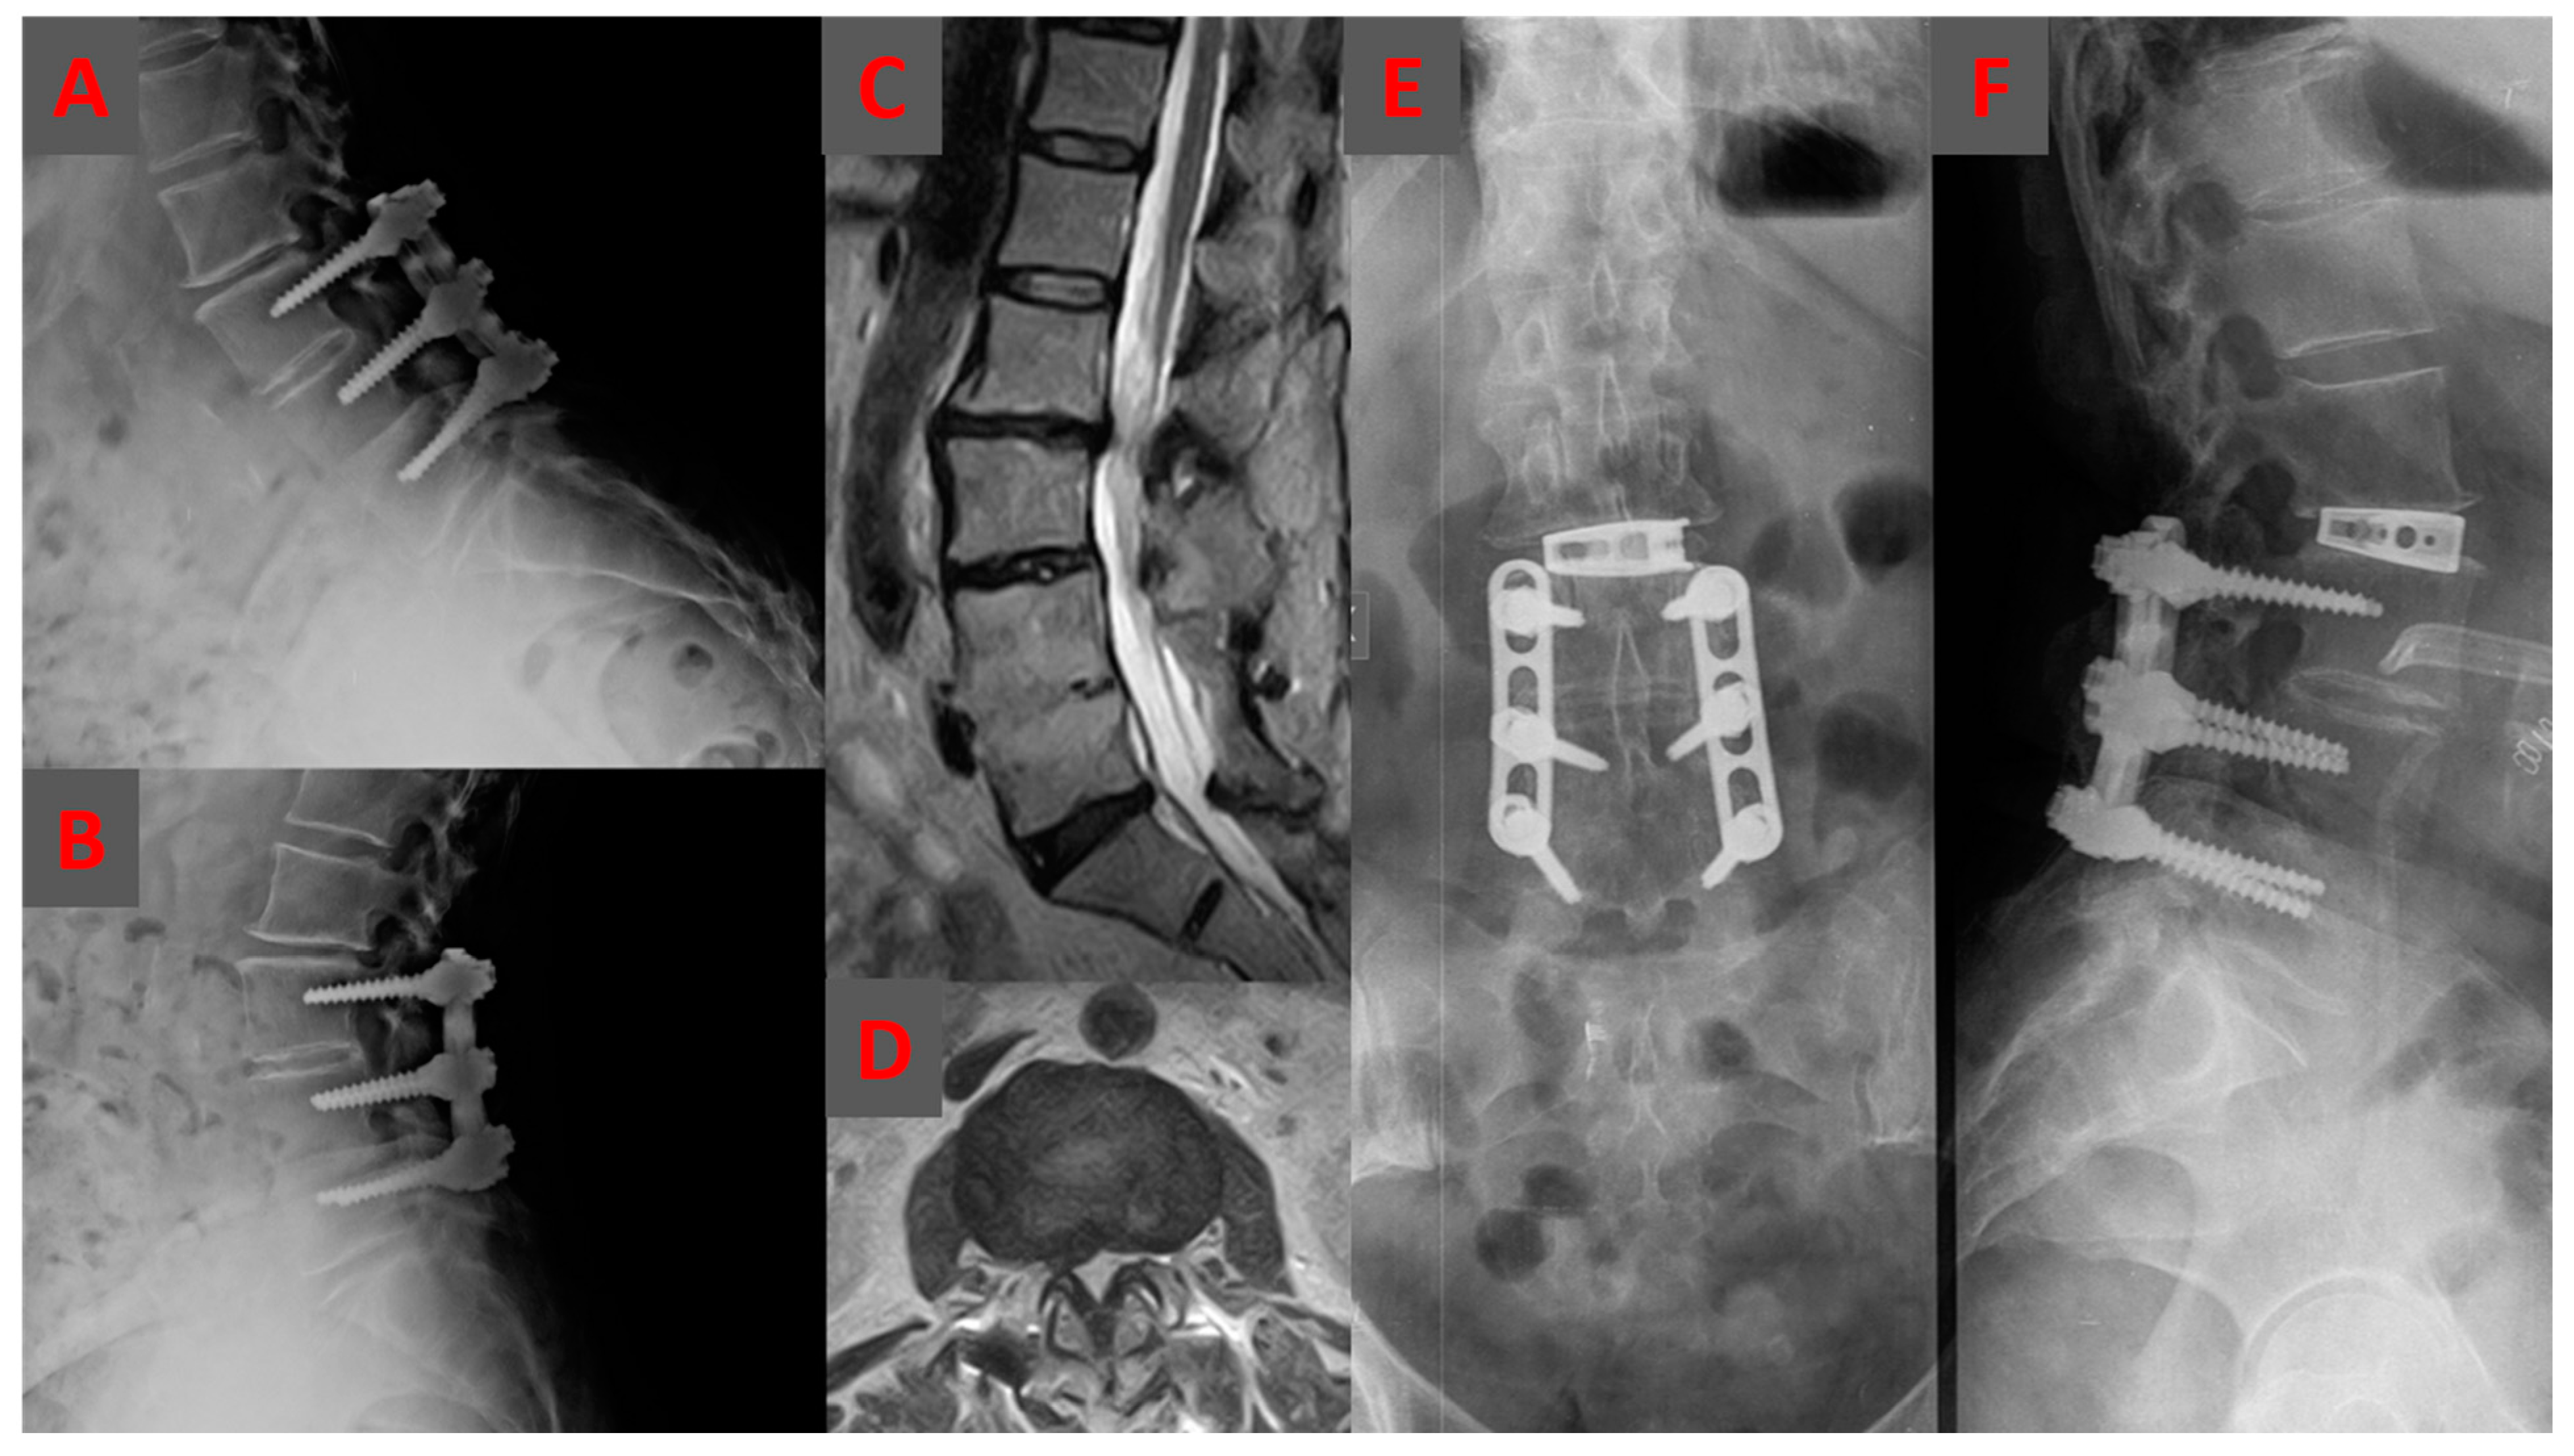

2.3.1. OLIF Group

2.3.2. Posterior Group